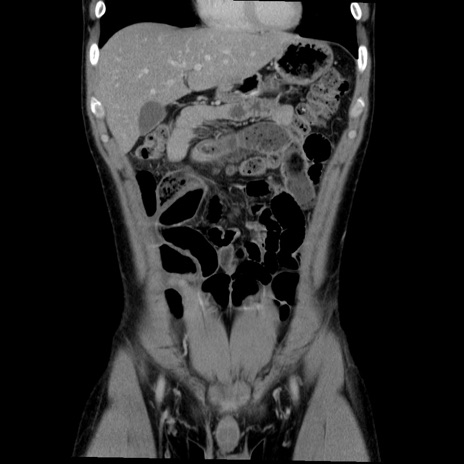

症例36(冠状断像)

【症例】20歳代 男性

【主訴】心窩部痛

【現病歴】今朝より上腹部痛あり。一旦軽快していたが再度出現したため救急要請。昨日夕に白身の魚を含む刺身を食べた。

【身体所見】BP 136/89mmHg、HR 74/min、BT 37.0℃、腹部:膨満、軟、心窩部に圧痛あり。反跳痛なし、筋性防御なし、腸雑音やや亢進あり。

【データ】WBC 17700、CRP 0.48